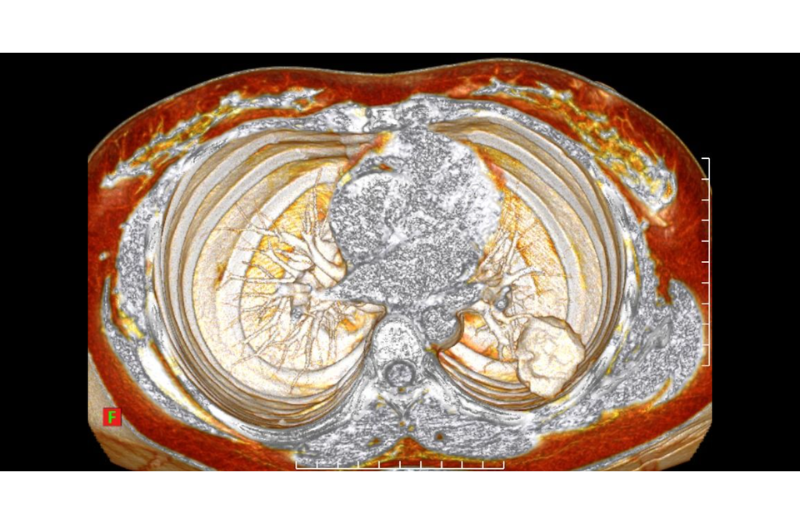

Hình ảnh chụp trên CLVT của bệnh nhân

Hình ảnh cắt lớp vi tính cho thấy khối tổn thương trong gan có cấu trúc không đồng nhất, bên trong có các vùng hoại tử và xuất huyết. Sau tiêm thuốc đối quang từ, tổn thương có hiện tượng tăng ngấm thuốc không đồng đều, trong khi một số vùng hoại tử không bắt thuốc.

Những đặc điểm này gợi ý một khối u ác tính giàu mạch máu – một đặc điểm thường gặp trong choriocarcinoma di căn.